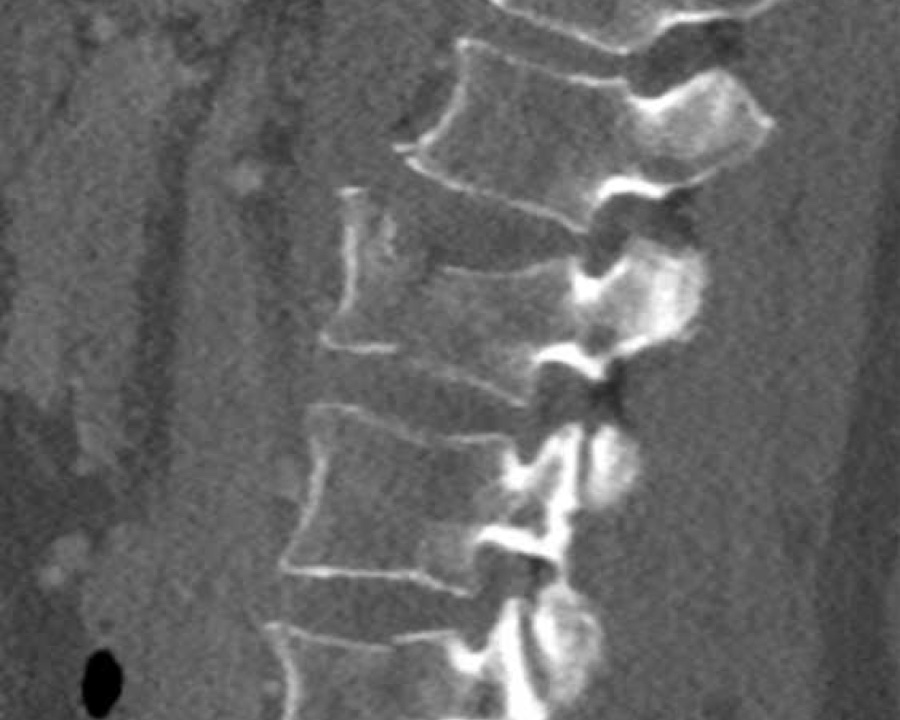

What is the highest AO-type of injury?

Findings:

- No C or B injury

- Fracture of the vertebral body with involvement of both endplates (1+1 points), no posterior wall involvement

Conclusion

injury type A2